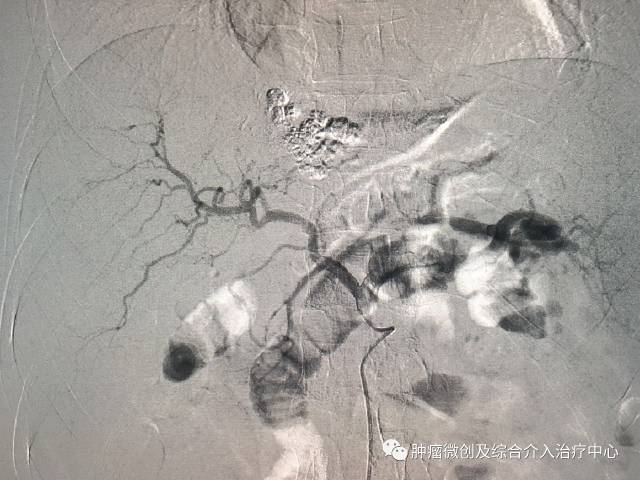

在肝癌中,血管性介入治疗临床应用最多。主要是选择性肝动脉灌注治疗,选择性肝动脉栓塞,选择性肝动脉化疗栓塞。其主要生理学基础是正常肝细胞的血液供应20%-25%来自肝动脉,75%-85%来自门静脉。而原发性肝癌的血液供应90%-95%来自肝动脉,这就为肝癌血管性介入治疗肿瘤提供了解剖学基础。三者具体技术方法是相同的,就是在皮肤上穿刺大概3-5mm的小口,从动脉内插管至肝癌供血动脉,再通过导管给药,不同之处在于给的药物不同。

是通过导管将栓塞剂选择性注入肿瘤血管和肿瘤供血动脉,阻断肿瘤供血,封闭肿瘤血管床,从而抑制肿瘤生长。这相当于把肿瘤“饿死”。常用的栓塞剂有明胶海绵,超液化碘油、海藻酸钠微球等。

选择性肝动脉化疗栓塞(TACE)就是经导管既给化疗药物,又给栓塞剂。通过两种途径消灭肿瘤。